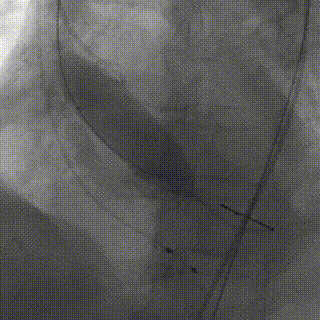

术中操作

冠脉造影

植入前造影

瓣膜定位

瓣膜释放

瓣膜植入后形态